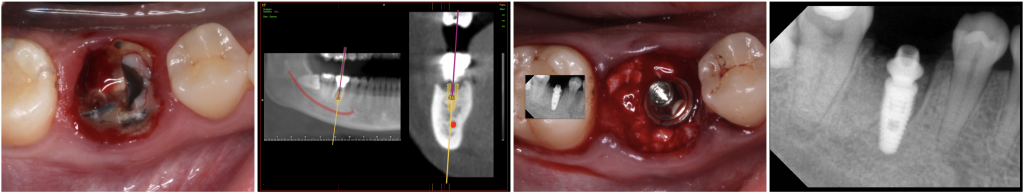

Fig. 1- Immediate Implant after extraction of a lower jaw first molar 46 (Neodent® Alvim), and placement of the definitive abutment (32 N.Cm).

The insertion torque range was 35 N to 60 N. The gap between the inner surface alveolar walls and the implant surface was filled with a grafting material (Instradent® Xenograft, cancellous 1.0-2.0mm, Nibec, South Korea) up to the implant platform. After implant insertion, a standard prosthetic abutments (2 CM abutments and 2 MiniCM abutments, Neodent) were connected (32 N) to the implants and the healing caps screwed (10 N) to the prosthetic abutments.

After the atraumatic extraction of the molars, the sockets were prepared following the implant system milling sequence, and four implants were inserted so that the shoulder of the implant was placed slightly to the septum and at least 2 mm beneath the bone crest. Implants of 3.5 or 4.3 mm diameter and 8 or 11,5 mm long were used (Alvim CM, Neodent).